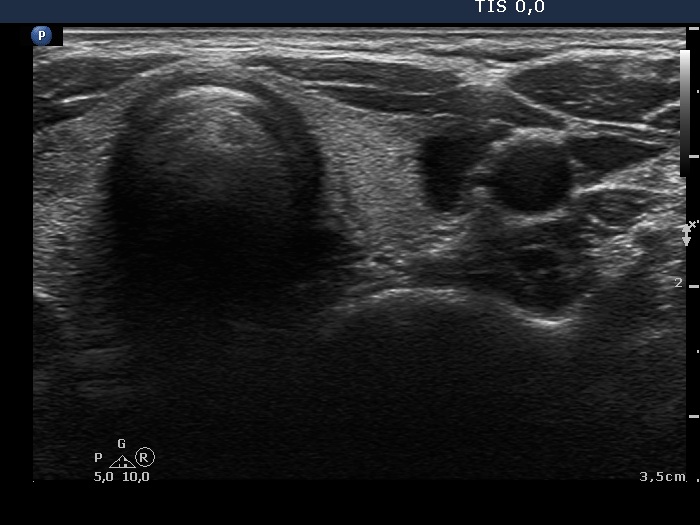

Second examination 3 years later (second row of images)

Clinical data: The patient had no complaints.

Palpation: unchanged.

Laboratory test: TSH 0.79 mIU/L.

Ultrasonography. Both the pattern and the size of the nodule in the right lobe remained unchanged. The cystic content of the left lobule has disappeared, it was replaced by inhomogeneous solid part. The vascularization of this lesion has also changed, the intranodular vascularization has become significantly increased.

Suggestion ultrasound in three years.

Comment. In the event of a cytological pattern which raises the suspicion of follicular tumor, we review the ultrasound records. By definition, a follicular tumor is surrounded with capsule. If none of the ultrasound signs of a capsule can be found, i.e. the nodule has neither halo nor perinodular blood flow than the risk of a follicular tumor is surely less than 5%. Be aware that more than 25% of cytologically suspected follicular tumors prove to be hyperplastic nodules on histopathology.